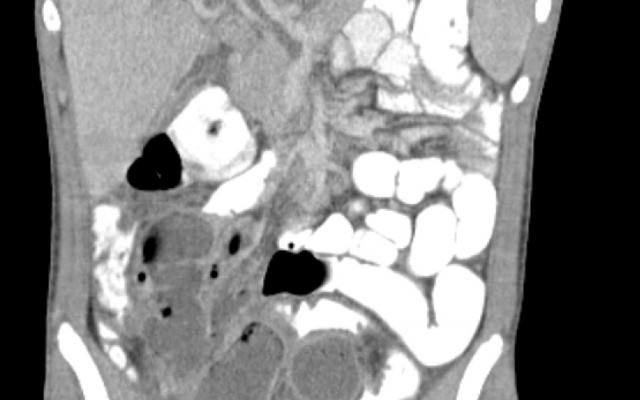

Dit artikel is alleen beschikbaar als PDF.Lees de PDF Artikelinformatie Online verschenen op 21 april 1976 Citeer dit artikel als Ned Tijdschr Geneeskd. 1976;120:1888-91 Heb je nog vragen na het lezen van dit artikel? Check onze AI-tool en verbaas je over de antwoorden. ASK NTVG Ook interessant Diagnose in beeld Een jongen met buikpijn, koorts en leverabcessen Nieuws Prognostische factoren bij pyogene leverabcessen Beeldquiz Een jongen met buikpijn, koorts en leverabcessen Meer gerelateerd … Reacties Login om een reactie te plaatsen